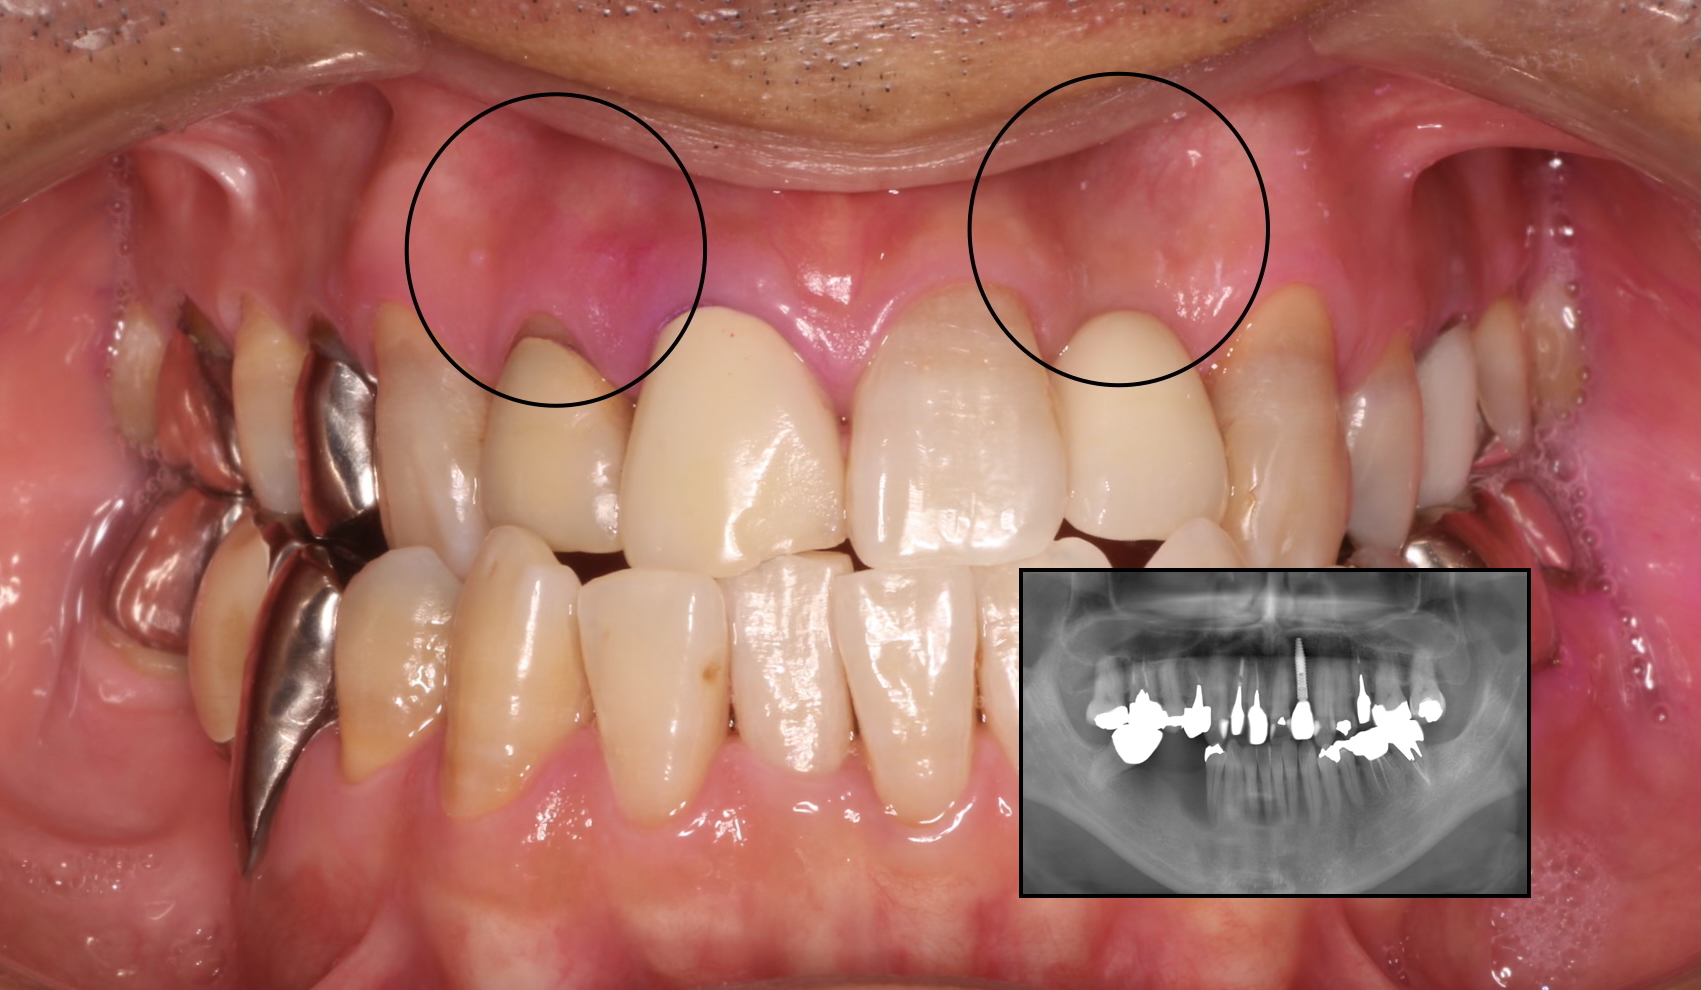

患者様は30代男性の方です。全身的な既往はありません。 右上前歯の痛みを主訴にご来院いただきました。

右上顎中切歯にレントゲン所見で僅かですが根尖部に限局した透過像と歯肉の腫れを認めました。

つまり、候補となりうる他の疾患との「鑑別」が重要になります。私が考えた鑑別診断は以下の2点ですが、結果として右上顎中切歯の根尖性歯周炎との診断の下、治療を開始いたしました。

VRF(垂直性歯根破折)との鑑別 レントゲン上で透過像が根尖部に限局している点、垂直性歯周ポケットを認めない点から、積極的に疑う所見がないと判断いたしました。ただしVRFは根尖側からクラックが入ることが多いため、最終的には被せ物を外してマイクロスコープを用い、視診で破折を確認します。(※CTやレントゲンでは完全破折以外は確定診断が難しい場合があります。)

隣在歯の根尖性歯周炎の可能性 根尖性歯周炎は、歯髄組織が壊死を起こしているか、過去に根管治療を施行された「失活歯」にしか発症しません。今回の症例では、右上顎側切歯および左上顎中切歯にEPT(電気歯髄診)で生活反応を示したため、消去法で原因歯は過去に根管治療を施行されている「右上顎中切歯」のみとなります。

本症例において、主訴ではない左上顎中切歯には「歯根の内部吸収」を認めました。レントゲン撮影時に偶発的に見つかった所見です。

歯根吸収は進行して歯質が菲薄化しており、いつ折れてもおかしくない状況でした。内部吸収は根管治療で進行を止められる可能性がありますが、失われた歯質は回復しません。残存歯質量の少なさから、保存的治療は困難と判断し、患者様にご説明いたしました。 (※永久歯の歯根吸収は原因不明なことも多いですが、お話を伺う限り、過去の外傷を起因とするものと推察されました。)